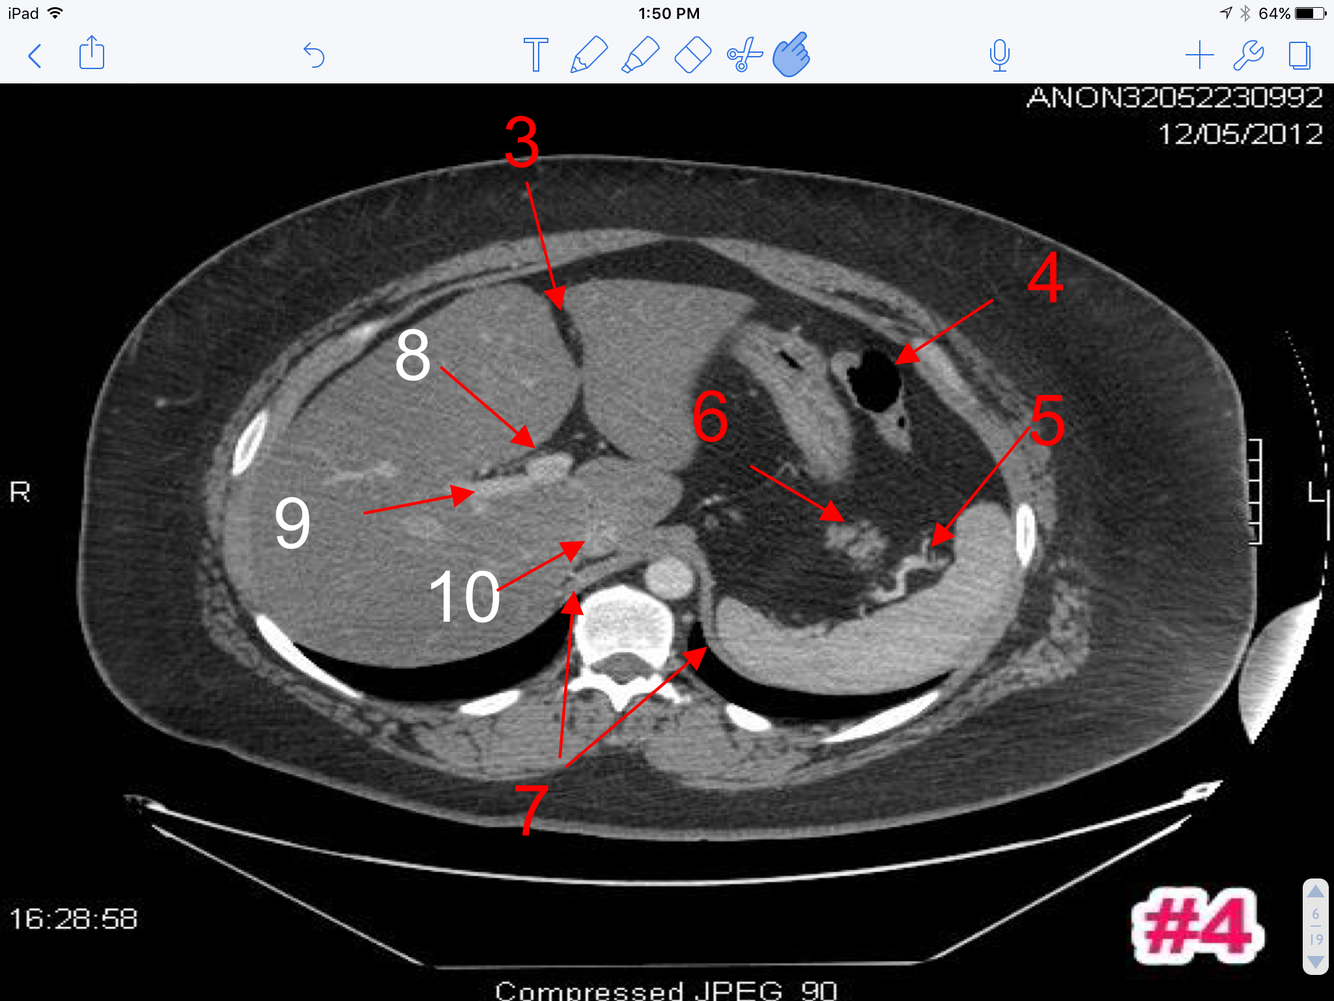

8

Q

A

1. Body of gallbladder

2. Portal vein

3. Inferior vena cava

4. Common hepatic artery

5. Body of the Pancreas

6. First part of the duodenum

7. Splenic vein

8. Splenic artery

11, Transverse colon

1. Descending colon